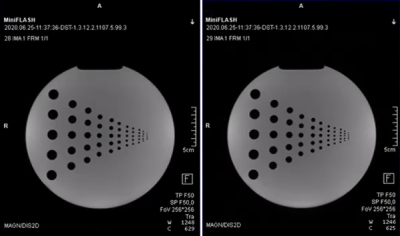

The prototype FLASH sequence and various deployment options successfully have been validated against the vendor's original implementation utilizing a sequence-diagram-based validation toolkit introduced earlier6. The scanner integration was successful, and images acquired with the prototype FLASH sequence show no visible differences to the original, see Figure 5.

The resulting images of the phantom scan. The left image shows the reconstructed image of the FLASH sequence directly implemented in the vendor’s software development environment. The right image shows the reconstructed image of the prototype FLASH sequence developed as Remote Sequence utilizing the commands provided by the interface. Both images were reconstructed using the same image reconstruction pipeline at the scanner.